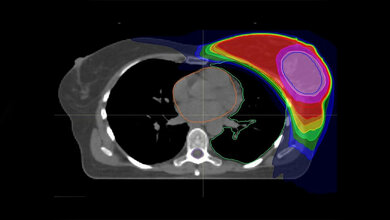

Alpelisib greift hemmend in den sogenannten PI3K-Signalweg ein, der bei Brustkrebs häufig durch Mutationen überaktiviert ist und so die Bildung von Tumoren begünstigt. Für Patientinnen mit diesen Mutationen fehlt es derzeit noch an wirksamen Behandlungsmethoden, vor allem wenn der Brustkrebs fortgeschritten ist und sich Metastasen bilden. Die Zulassung von Alpelisib war deshalb mit großen Erwartungen verbunden. „Es hat sich aber leider herausgestellt, dass der Erfolg des Medikaments durch Resistenzen stark eingeschränkt wird“, sagt Prof. Dr. Mohamed Bentires-Alj, Leiter der Forschungsgruppe. „Daher ist es dringend erforderlich, mehr über die Entstehung von Resistenzen herauszufinden.“ Sein Team suchte deswegen nach den genetischen Grundlagen der Resistenzen, also nach jenen Genen, deren Veränderung Krebszellen resistent macht. Das Resultat: Mutationen, die das Protein NF1 ausschalteten, machten die Tumore resistent gegen die Behandlung mit Alpelisib. Es ist bekannt, dass NF1 über verschiedene Signalwege das Wachstum von Tumoren unterdrückt, jedoch wurde das Gen noch nicht mit der Resistenz zu Alpelisib in Verbindung gebracht.